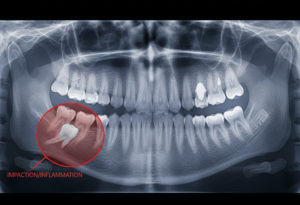

Часто зубы мудрости не могут нормально “проклюнуться” из-за недостатка пространства в уже сформированной челюсти, расположены аномально или непосредственно под костью. Симптомы неправильного роста зуба мудрости достаточно яркие. Отмечается выраженный болевой синдром, который может отдавать в ухо или горло, припухлость щеки. Травматизация слизистой сопровождается кровоточивостью. При таких ситуациях может потребоваться удаление.

Для уточнения необходимости экстракции доктор порекомендует рентгенографию, чтобы оценить положение зубов и их влияние на соседние структуры. Если зубы мудрости показывают потенциальные проблемы, такие как

- развитие кисты

- повреждение соседних зубных единиц за счет кривого роста

- смещение имеющихся зубов, приводящих к нарушению прикуса

- периодонтит

- кариес “восьмерки” при плохом доступе для лечения

Это служит показанием для удаления.